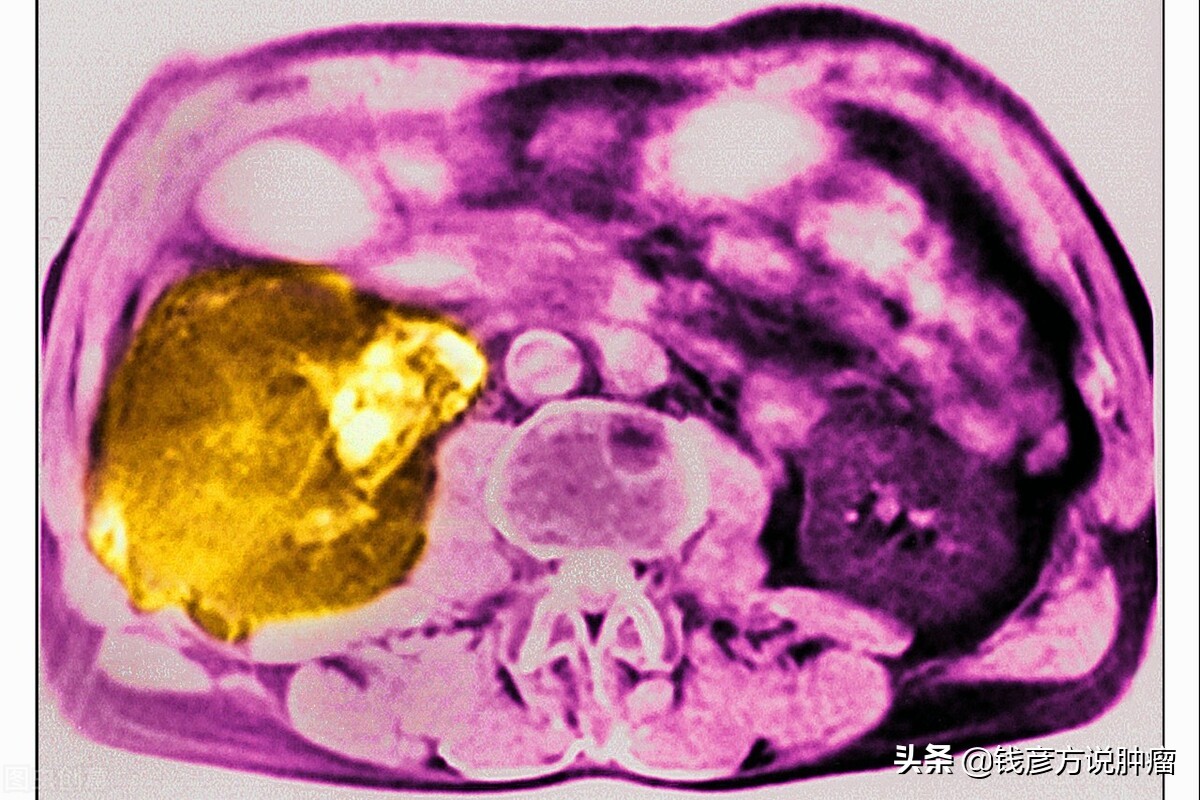

原来是15公分大的肝癌,这名患者没选择做手术,经过几年服用中药的治疗以后,病灶一点一点地在长,但是这个病灶最大的特点就是没出现转移的现象,最后病灶竟然达到了惊人的18公分。

癌症在临床上往往会出现很多复杂且多样的病人,我记得在八年前有一个这样的病人,来的时候,在肝部有一个巨大的肿瘤,当时在北京比较知名的医院,明确诊断为,在肝的右叶有一个15.5公分大的肿物。

后来给这名患者做了穿刺,结果确定为胆管细胞癌,然后就以这个治疗原则为主继续治疗,肿块也逐渐变成了低密度影,意味着液化、坏死,肿块周围有一层类似包膜的物质。